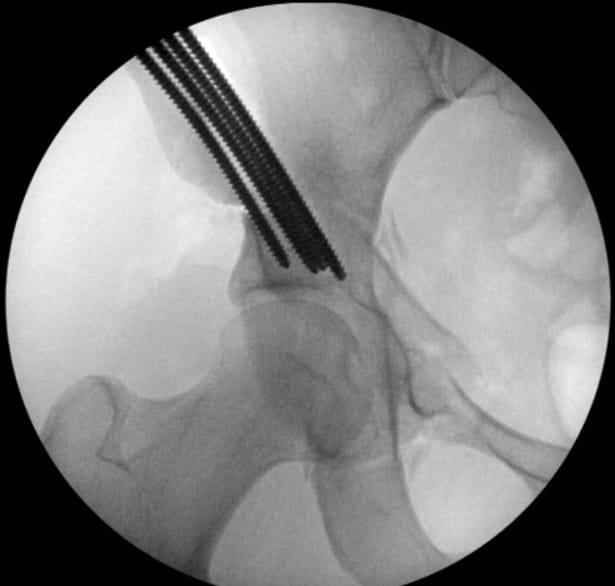

Most surgeries take place at UH Beachwood Medical Center, a state-of-the-art hospital offering specialized orthopedic services. The team pioneered the use of the Stryker Pivot Guardian table for post-less hip distraction for its combined procedure, reducing interoperative risk and maximizing OR efficiency. As the single-table technique utilizing the Stryker system grows in popularity around the country, University Hospitals has become a training site for its innovative design and capabilities.

Without disrupting the sterile surgical field, Dr. Wetzel next scrubs in and employs an open technique to deepen and reorient the hip socket. “Where University Hospitals differs from other places around the country is that we have been able to maintain a partnership that requires two very vastly different skill sets to execute this surgery to the highest level of efficiency and skill,” he says. “We have the ability to rely on each other as knowledge sources and eliminate single-surgeon bias when we discuss treatment plans with patients.”